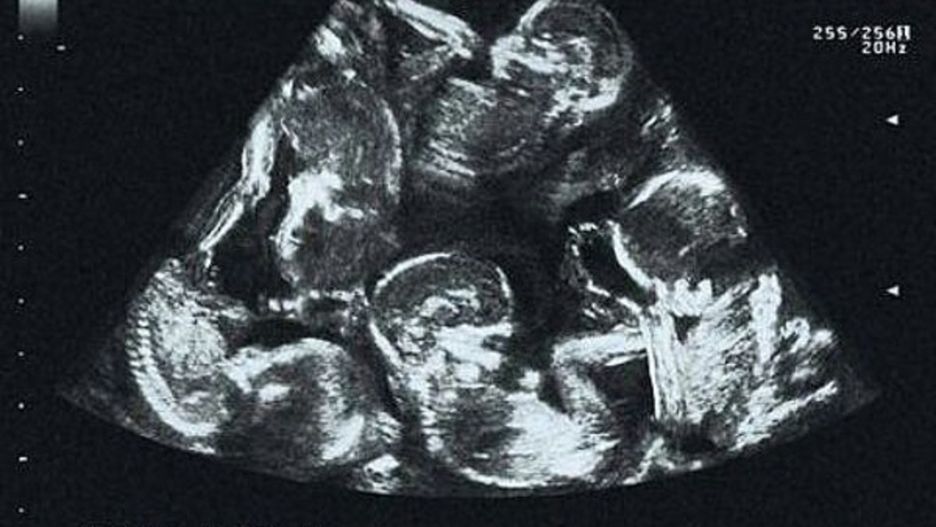

Niezwykłe zdjęcie z USG. Ile dzieci widzisz?

Kolejne badania sprawiły, że Alexandra była jednocześnie zachwycona i przerażona. Okazało się, że prawdopodobnie urodzi trojaczki. Jednak wraz z upływem tygodni, łatwiej było dostrzec płody. Wtedy też młodzi rodzice usłyszeli, że na świecie powitają nie dwoje, troje, nawet nie czworo dzieci, a pięcioraczki!

Niezwykłe zdjęcie z badania USG szybko trafiło do mediów społecznościowych, a Alexandra stała się pierwszą matką pięcioraczków w Czeskiej Republice.

Zdjęcie USG

Zdjęcie USG © Facebook